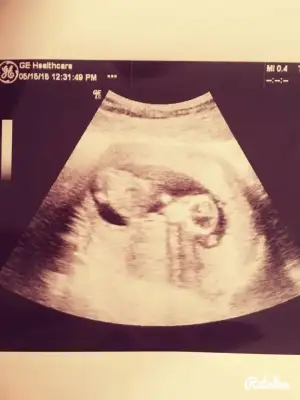

kızlar merhablar şimdi kontrolden geliyorum nolur bi bakın :))) sizce cinsiyetimiz ne ? 12. haftayı doldurduk bugün